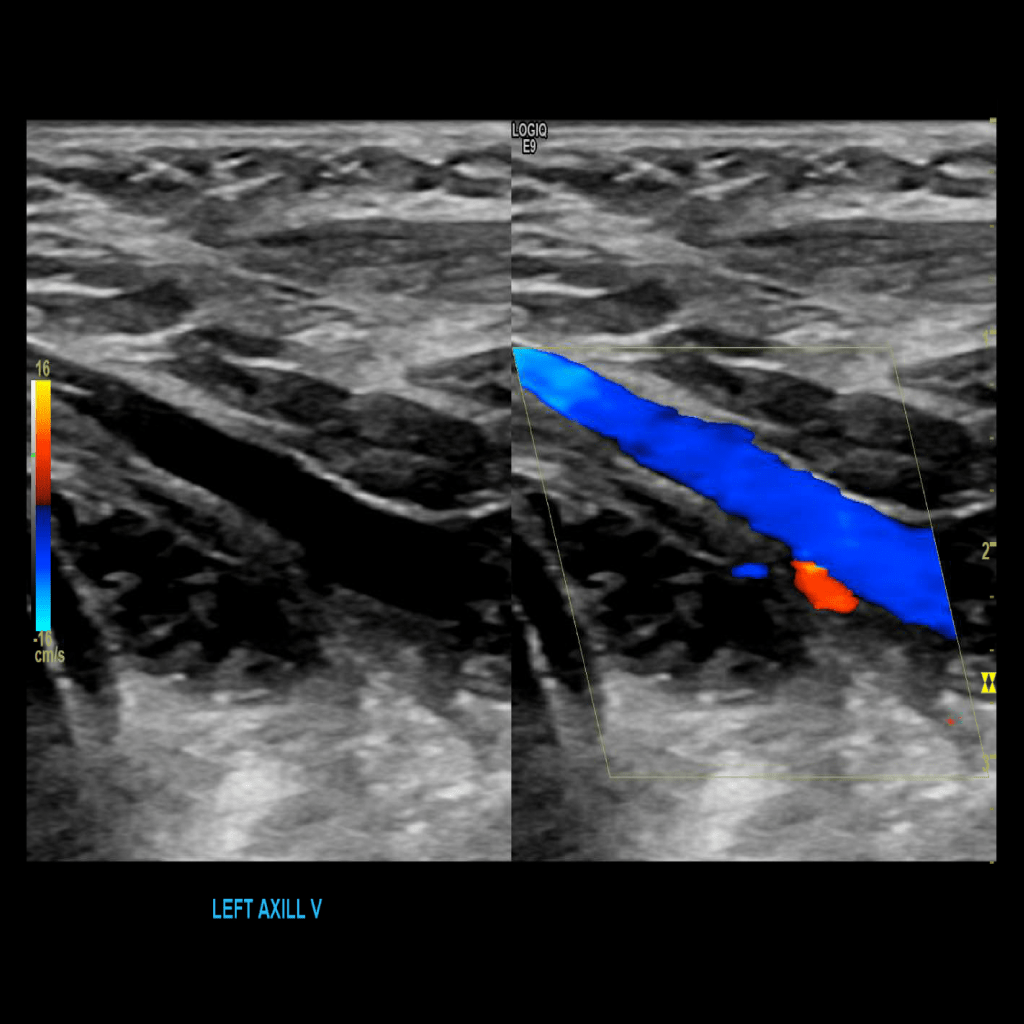

Scan the axillary vein in grey scale, compression, color doppler and spectral doppler